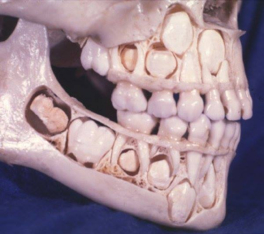

Formado por: boca, faringe, esófago, estómago, intestino delgado, intestino grueso, recto y ano. Su pared está compuesta de 3 capas: Una capa muscular longitudinal. Una capa muscular circular. Una capa interna de tejido epitelial o mucosa, con glándulas que producen mucus y jugos digestivos. Las capas musculares le dan elasticidad y movilidad (peristalsis). LA BOCA Orificio de entrada al digestivo. Cerrada por los labios. En su interior está la lengua, órgano muscular que ayuda a la masticación, deglución y percepción de sabores. La boca se comunica con la faringe o garganta, común a digestivo y respiratorio. DIENTES Los dientes son las partes más duras del cuerpo humano. Se encuentran alojados en cavidades de la mandíbula llamadas alveolos y unidos a las encías. Un diente tiene las siguientes partes: Existen cuatro tipos de dientes: Incisivos: (paletas). Corona plana y afilada. Sirven para cortar los alimentos. Caninos: con corona puntiaguda. Para desgarrar. Premolares: de corona ancha y aplanada. Para aplastar y triturar Molares: de igual forma y función que los premolares, pero mayores y con 3 raíces. Los humanos tienen dos denticiones. La primera aparece a los 6 meses y dura hasta los 6 años. Consta de 20 dientes (todos menos los molares). Es la llamada dentición de leche. La 2ª aparece a partir de los 6 años, sustituyendo a la anterior y añadiendo los molares, con lo que consta de 32 dientes. Es la dentición definitiva. FARINGE Garganta. Cavidad común al digestivo y al respiratorio. ESÓFAGO Tubo de 25 cm. Conecta la boca y el estómago, atravesando el diafragma. Se halla entre la tráquea y la columna vertebral. ESTÓMAGO Órgano en forma de saco. Capacidad de litro y medio. Tiene un orifico de entrada (cardias), comunicado con el esófago y controlado por un esfínter (músculo circular) y otro de salida (píloro), que lo comunica con el intestino delgado gracias a otro esfínter. La pared interna tiene una mucosa protectora y glándulas que fabrican el jugo gástrico. El estómago almacena el alimento y lo digiere en parte, controlando su paso al intestino. INTESTINO DELGADO Tubo largo y delgado, de unos 5 metros, por lo que se halla enrollado en el abdomen. Se divide en tres partes: Duodeno: primer tramo. Unos 25 cm. A él vierten los conductos biliares y pancreáticos. Yeyuno: parte media. En él se da principalmente la absorción. Íleon: porción final, y más larga, del intestino, donde se acaban de absorber los nutrientes. Desemboca en el intestino grueso por la válvula ileocecal. La pared del intestino delgado está muy plegada para aumentar su superficie de absorción. Además, estos pliegues presentan otros menores con forma de dedo llamados vellosidades, cuyas células tienen repliegues de la membrana denominados microvellosidades. De esta forma se consigue una superficie total de varios m 2 . INTESTINO GRUESO Tubo más grueso y corto que el intestino delgado. Mide 1,5 m y unos 10 cm de grosor. Se divide en: Ciego: primera porción, con forma de fondo de saco y con una prolongación de unos 7 cm llamada apéndice vermiforme. Colon: parte más larga, con forma de ‘U’ invertida. presenta una porción ascendente, una transversa y una descendente. Recto: última porción. Acumula las heces antes de su salida al exterior. ANO Orificio de salida del digestivo, situado al final del recto, y controlado por el esfínter anal. A través de él se expulsan las heces al exterior.